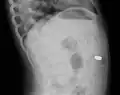

AP X ray showing a 9mm battery in the intestines